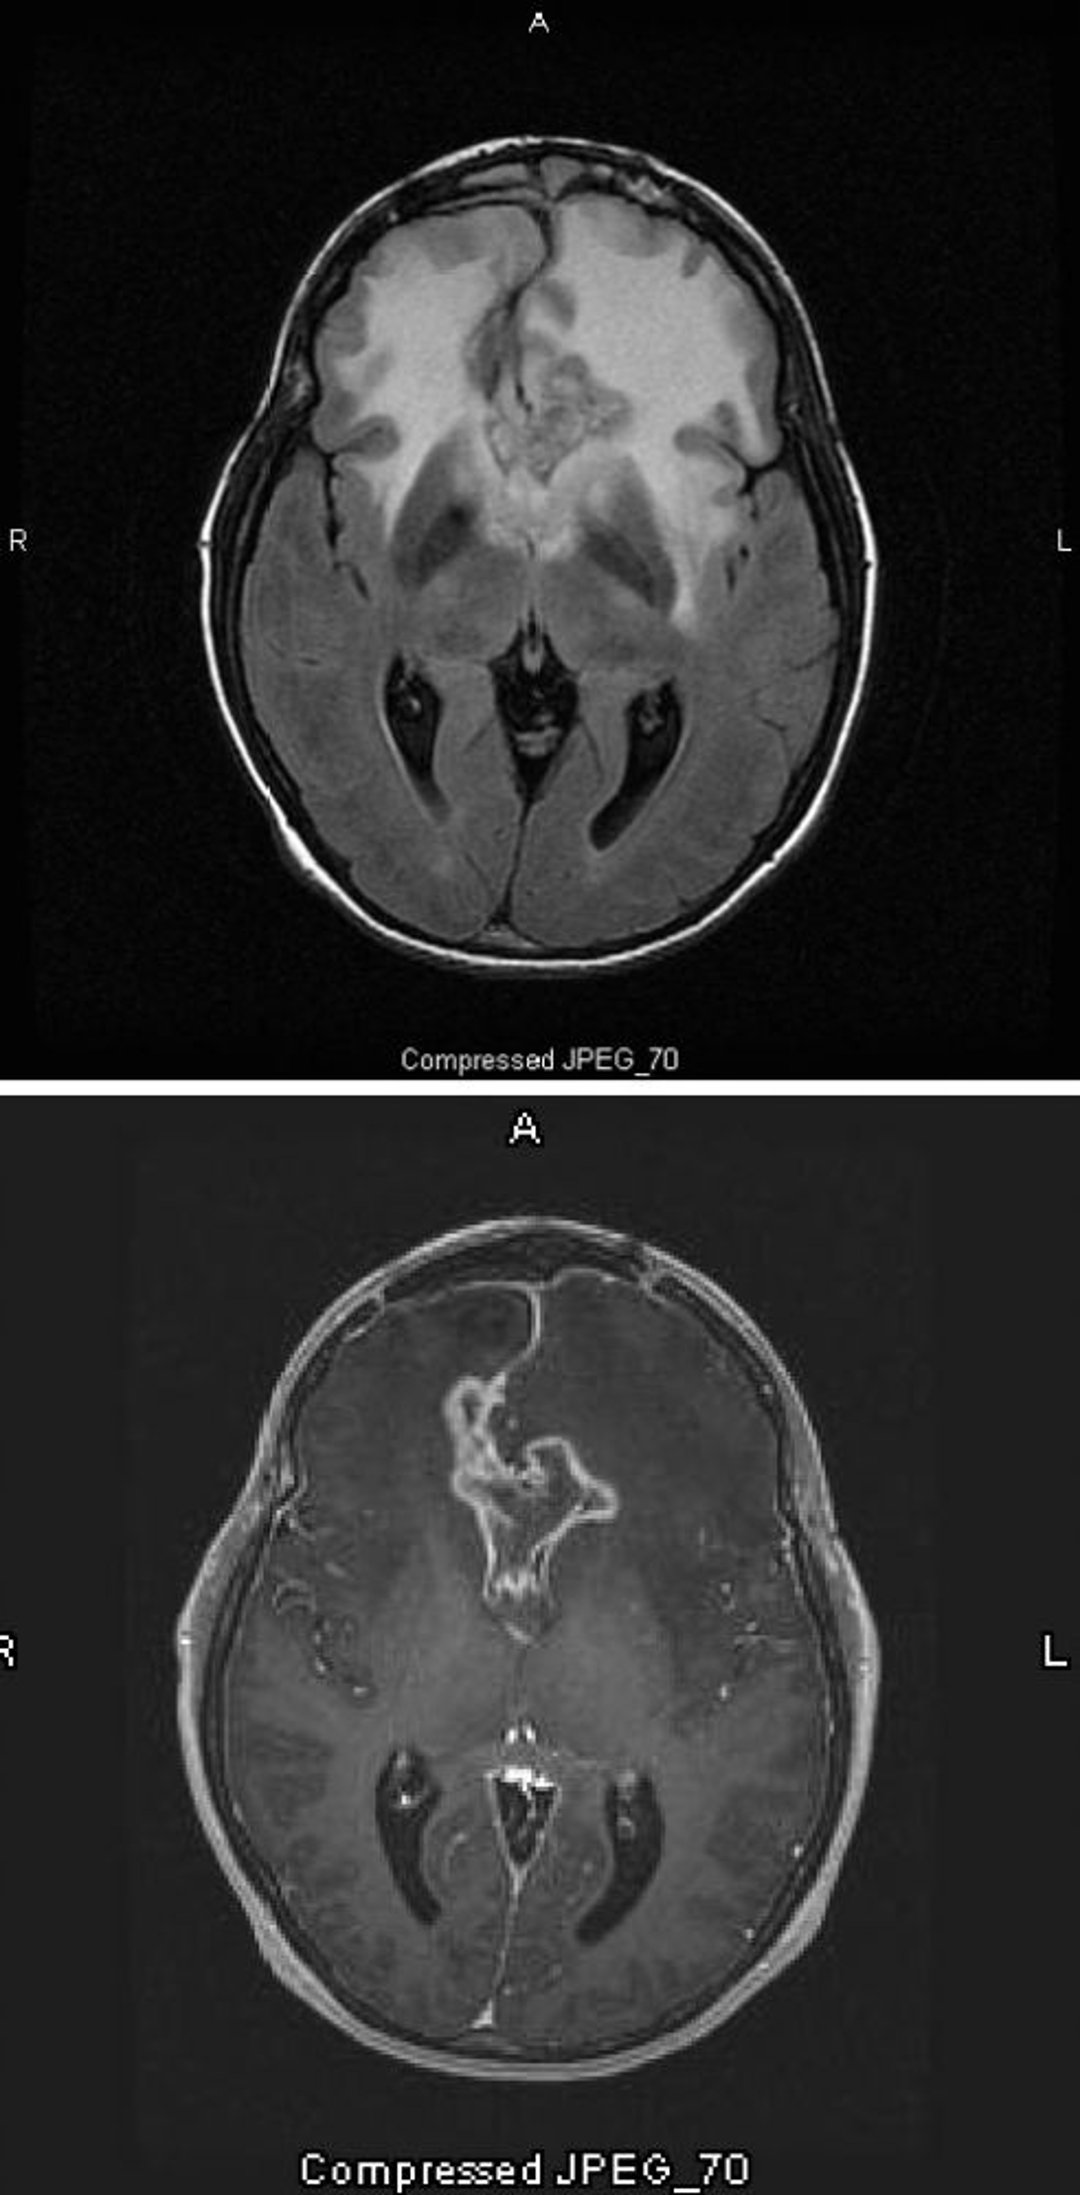

Снимок T2-FLAIR МРТ (вверху) показывает большой двусторонний сигнал белого цвета (с повышенной плотностью) вокруг глиобластомы, которая является самой злокачественной и наиболее злокачественной астроцитомой. Эта специфическая глиобластома называется "глиомой бабочки", поскольку распространяется по полушариям, формируя крылья бабочки; это вызвано отеком мозга. На T1-взвешенном изображении (внизу) контраст очерчивает край опухоли (усиление окружности). Отек проявляется в виде затемненного участка (гипоинтенсивность) на T1.

Images courtesy of William R. Shapiro, MD.